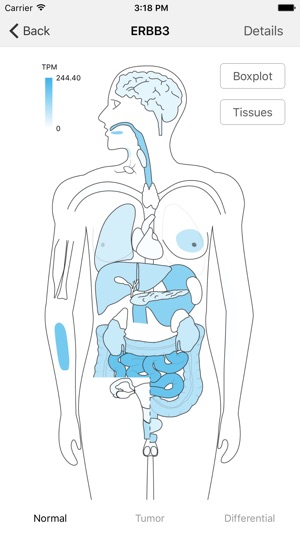

This GE-mini APP is designed to exhibit gene expression profiling of a given gene over many tissue types including tumors. The underlying data are based on RNA Sequencing results from both TCGA and GTEx after they are normalized and integrated. The current version, based on the September 2015 release of TCGA and the phs000424.v6.p1 release of GTEx, contains >19,000 total samples across 33 cancer types and 53 normal tissue types.